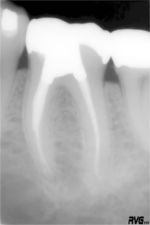

歯科の領域は硬組織(こうそしき)の世界です。硬組織とは骨や歯のように文字通り硬い組織のことで、これに対して人間の身体のそのほかの部分を構成しているのは軟組織です。レントゲンは身体の表面からは見えない部分を覗き見て病気の診断などをするためには欠かせないものですが、レントゲン線には軟組織は通過しやすく硬組織は通過しにくいという性質があります。そのため歯や骨を含む組織をレントゲンで撮ると、フィルムの上に通りにくい歯や骨と通りやすい筋肉や血管との間に濃さの差が出てきます。フィルムはもとも と白いので通りにくい骨の部分は白っぽく、そのほかの部分は黒々と焼かれます。もし骨や歯が病気で侵されていると白いはずのところが黒くなって見えます。軟組織に病気があるときにはわかりにくいのでわざわざ造影剤というものを入れて組織が白く写るようにしておいてその白い形を正常なものと比較して診断します。

歯科領域では顎の骨が異常に増殖したり、余分の歯があったりする場合以外は、ふつう病気の箇所は黒っぽく見えます。